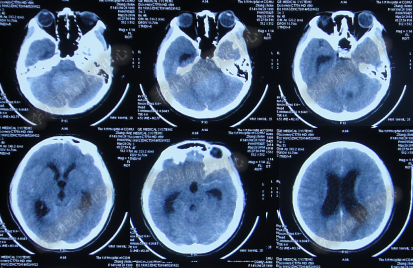

2014年8月31日住入李小勇脑脊液中心,入院时:卧床,表情淡漠,神志嗜睡;体温高37.9°C;头颅枕后正中手术瘢痕,结痂尚未脱落;左枕侧脑室外引流固定在位,尚通畅,可见淡红色浑浊脑脊液引出;颈抵抗,双肺呼吸音粗(图-27);头部CT检查示(小脑肿瘤术后颅内感染病例)脑室系统粘连严重伴双侧颞角脑室扩张明显,双侧侧脑室见引流管影,脑内见多发斑片低密度,中线结构无移位,颅骨术后改变(图-28)。

图-27:2014年8月31日入院时

图-28:2014年8月31日头部CT

入院第4天即2014年9月3日,左枕脑室外引流管引流脑脊液量不多,晨起4:00左右出现血压升高伴瞳孔扩大,4.5:2.0;多参数生理:心率102次/分,呼吸11次/分,血压141/96mmHg,血氧饱和度98%;急行头部CT检查示双侧侧脑室扩大,颞角扩张显著,双侧侧脑室见引流管影,位置变化不大,脑内见多发斑片低密度(图-29)。

图-29:2014年9月3日4点50分头部CT